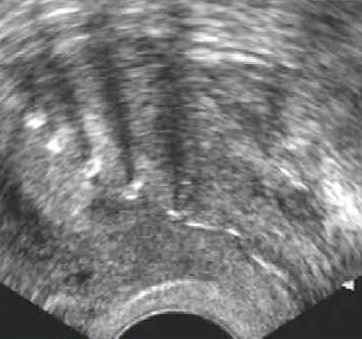

Эндометрия плоха растет

Эндометрия плоха растет 112 фотографий